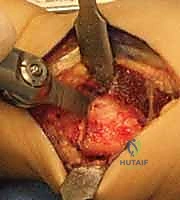

عملية تقصير عظم الكعبرة هي إجراء جراحي فعال لعلاج مرض كينبوك، وهو نخر لاوعائي يصيب العظم الهلالي في الرسغ. تهدف العملية إلى تخفيف الضغط عن العظم الهلالي وإعادة توزيع القوى داخل الرسغ، مما يقلل الألم ويوقف تطور المرض. يقدم الأستاذ الدكتور محمد هطيف في صنعاء هذه الجراحة بدقة عالية.

الخلاصة الطبية السريعة: عملية تقصير عظم الكعبرة هي إجراء جراحي دقيق وفعال يُستخدم بشكل رئيسي لعلاج "مرض كينبوك" (Kienböck's Disease)، وهو حالة من النخر اللاوعائي تصيب العظم الهلالي في مفصل الرسغ. تعتمد فكرة العملية على تقصير عظم الكعبرة بمقدار مليمترات قليلة لتخفيف الضغط الميكانيكي الهائل الواقع على العظم الهلالي، وإعادة توزيع القوى داخل الرسغ بشكل متوازن. يؤدي ذلك إلى تقليل الألم بشكل ملحوظ، إيقاف تدهور العظم، وتحفيز التروية الدموية. يُعد الأستاذ الدكتور محمد هطيف، أستاذ جراحة العظام والمفاصل بجامعة صنعاء واستشاري جراحات العظام الدقيقة، الخبير الأول في اليمن لإجراء هذه الجراحة المعقدة بأعلى نسب النجاح.

عندما يفشل العلاج التحفظي، أو عندما يتم تشخيص المريض في المرحلة الثانية أو الثالثة، يصبح التدخل الجراحي هو الحل الوحيد لإنقاذ الرسغ. يقدم الأستاذ الدكتور محمد هطيف أحدث التقنيات الجراحية العالمية في هذا المجال.